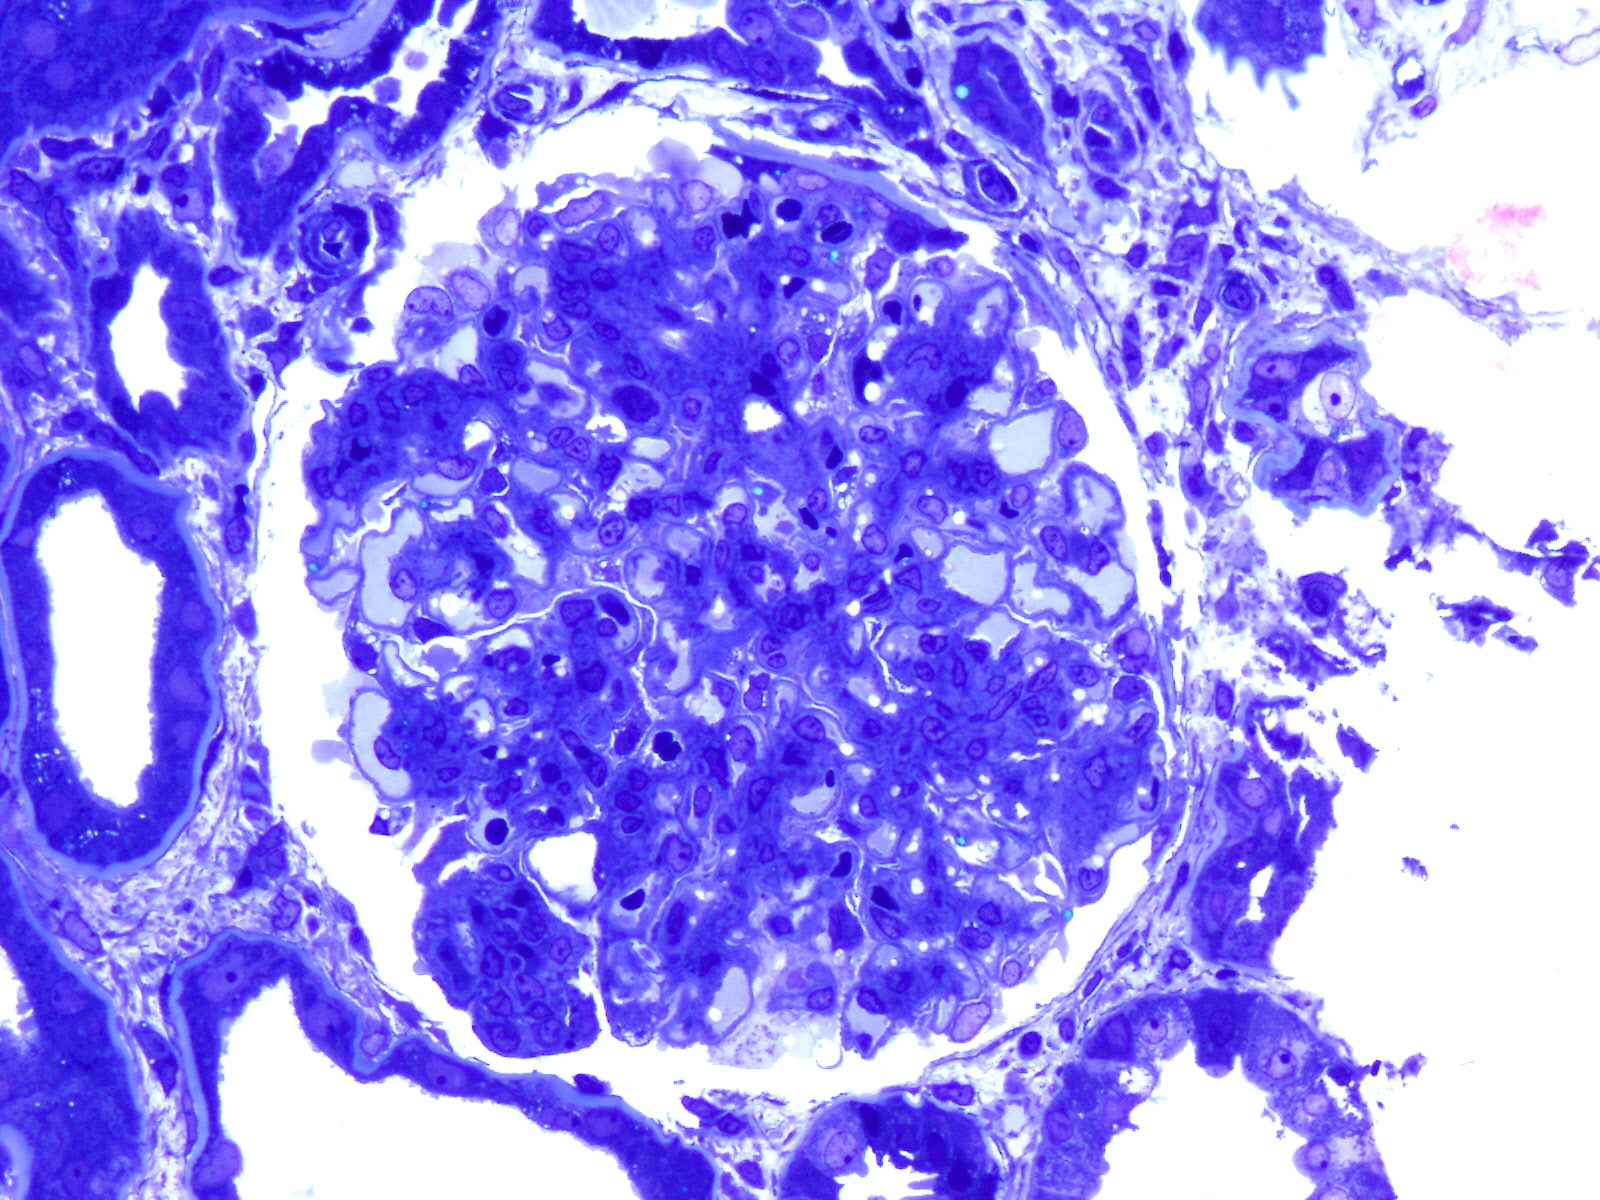

- 1.0cm to 3.0cm of cortex with glomeruli for formalin, LM